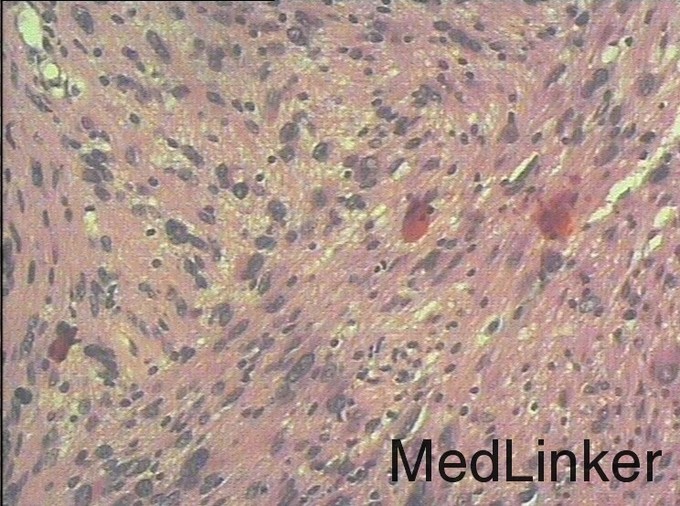

随访:术后病理结果提示:(右侧桥小脑角处肿物)肿瘤由梭形细胞构成,可见疏区及密切,部分细胞呈栅栏状排列,细胞有异型性,核分裂可见,间质有散在淋巴细胞浸润,结合免疫组化结果,符合神经鞘瘤。 讨论:听神经瘤是桥小脑区最常见的肿瘤,也是最常见的脑神经瘤,绝大多数病理类型为神经鞘瘤。下面结合本例影像学习一下其影像表现:首先就是部位,发生于桥小脑区的占位第一反应是听神经瘤,而且和岩骨是呈锐角相交,该征象可以和发生于该部位脑膜瘤鉴别。另外,肿瘤沿听神经长如,导致内听道扩大也是一个重要征象。增强扫描可见明显强化,这可以和发生于该部位的胆脂瘤鉴别。